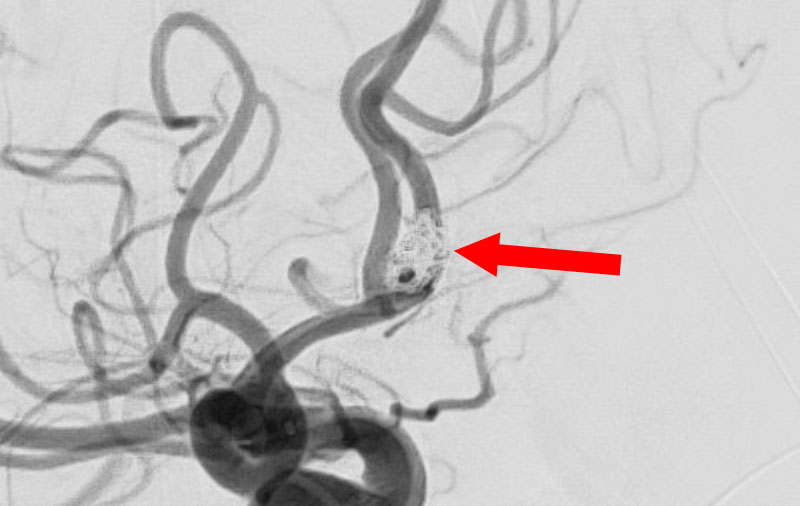

くも膜下出血

左中大脳動脈瘤破裂

40代

救急外来

No.1596 手術中